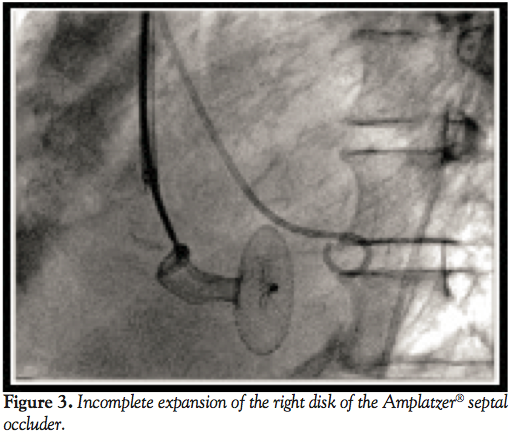

A right internal jugular venous access is usually needed for defects located in the mild apical or posterior septum.2 The delivery sheath was advanced through the jugular vein into the LV (Figure 2) where the tip of the sheath was placed. After removing the delivery sheath dilator and wire, the loaded flexible Amplatzer® device (AGA Medical Corp.) was advanced through the delivery sheath across the septal rupture into the LV. The device was pushed partially out of its catheter sheath until release of the first disk. A 24 mm Amplatzer® muscular VSD occluder was implanted (AGA Medical Corp.), but pulled through into the right ventricle before the detachment. A 26 mm Amplatzer® septal occluder (AGA Medical Corp.) was then implanted without adequate expansion of the right disk (Figures 3 and 4) due to the long and tortuous tract with residual persistent shunting.

In our case, available VSD occluder device size was not sufficient to fully close the VSD. In consequence, an atrial septal defect (ASD) occluder was used, which led to suboptimal device deployment of the RV disc due to the length of the waist with persistent shunting.